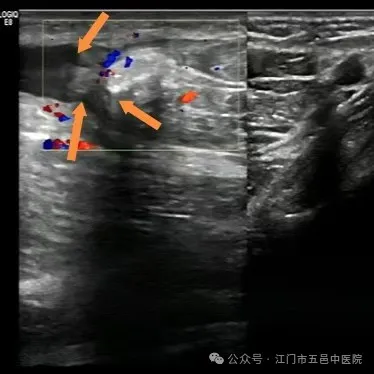

近日,小帅忐忑不安地来到江门市五邑中医院运动医学科就诊,科室医生安排他进行了肌骨超声检查,报告提示其“右侧肱二头肌长头腱完全断裂”!

▲举杠铃引起的肱二头肌长头腱完全性断裂